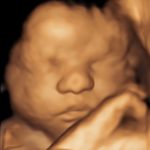

4D/5D/HD Ultrasound Gallery

Gallery